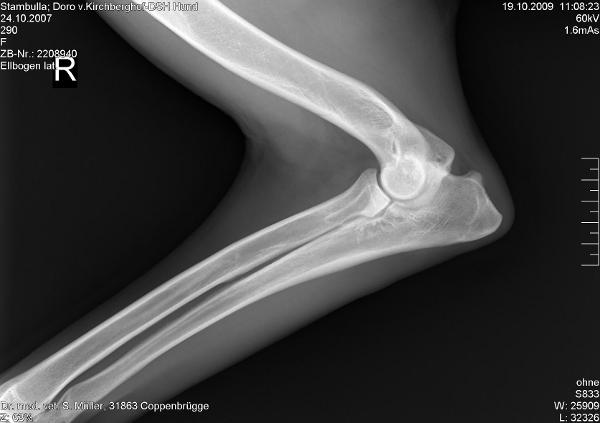

HD/ED:

a-fast-normal              a-noch zugelassen